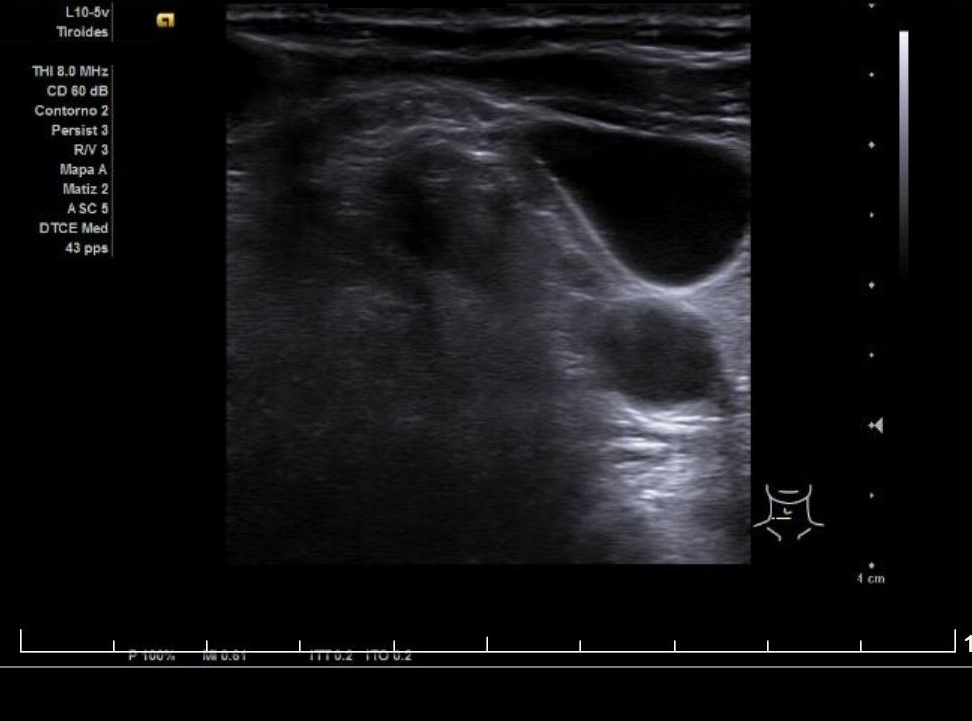

Descripción de los hallazgos ecográficos y las imágenes más relevantes para la resolución del caso

Se aprecia un tiroides de características ecográficas compatibles con tiroiditis, sin cambios respecto a ecografía previa, al igual que la grasa peritiroidea derecha, pero de manera incidental se observa un aumento del calibre fusiforme de la yugular externa derecha con respecto a la izquierda, con flujo vascular reducido.